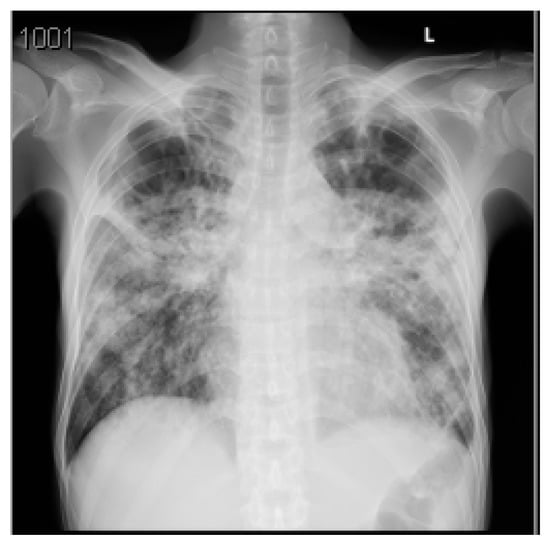

A summary of his laboratory and radiological investigations are described in Table 1 and Figure 1, respectively.

A CT chest with contrast was completed to confirm the CXR findings and was reported as: ‘Bilateral multiple patchy cavitating consolidations larger at the apical posterior segment of left upper lobe, differential diagnosis includes cavitating pneumonia, fungal infection or TB, especially with the involvement of the the apicoposterior segment and less likely to represent septic emboli’. The patient was admitted to the intensive care unit (ICU) with the impression of COVID-19 or TB pneumonia and acute coronary syndrome. The patient was examined by the Cardiology and Gastroenterology teams, who ruled out any significant conditions and placed him on conservative therapy.

Figure 1. Posteroanterior chest X-ray (CXR) of the first case. The CXR shows bilateral diffuse patchy opacities noted with left upper lung zone consolidation, which could be infectious for clinical correlation and follow-up. Perihilar peribronchial thickening noted. No pleural effusion or pneumothorax. The cardiomediastinal silhouette appears unremarkable.